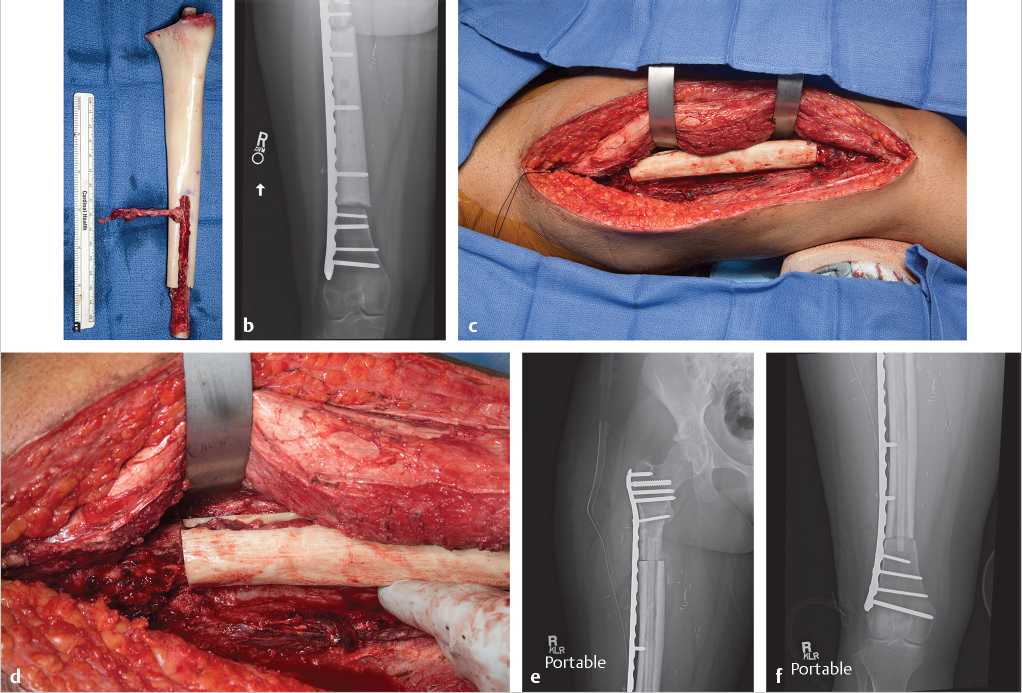

Fig. 23.1 (a) Anteroposterior radiograph of a 59-year-old woman with chronic osteomyelitis (arrow) of her right tibia as a result of an open fracture treated over 10 years ago. (b) Initial management consists of bone debridement, antibiotic bead placement for 6 weeks, and (c) external fixator placement for stability during treatment process. (d) A free fibula flap with a skin paddle is chosen for definitive treatment of the bone defect. Flap design begins by identifying Doppler signals in the skin (marked with X) just posterior to the fibula border, which correspond to cutaneous perforators for designing the skin island. (e) Dissection begins by elevating the anterior aspect of the incision until one identifies the interval between the peroneus muscles and the soleus. The fascia covering the peroneus muscle is elevated to reveal the perforators passing posterior to the fibula in the posterior crural septum. (f) Once the perforators are clearly identified the posterior margin of the skin island can be dissected. The major cutaneous perforator can be seen in this image along with the anterior and lateral dissection over the fibula. (g) The distal osteotomy is made with the aid of a Chandler retractor placed beneath the fibula to protect the peroneal vessels. (h) The common peroneal nerve (shown at the tip of the scissors) is identified at the superior margin of the incision prior to completing the proximal dissection and proximal osteotomy. (i) Once the proximal osteotomy is performed, the peroneal vessels are dissected back to the tibial peroneal trunk. (j) The fibula is now entirely isolated on its vascular pedicle. (Continued) (k) An image of the flap prior to insetting. (l) The leg is maintained in external fixator until definitive bony union. An elastic band attached to the fixator is used to prevent Achilles contracture. (m) Lateral radiograph showing insetting of the fibula using two compression screws. (n) Lateral radiograph of healed bone. (o, p) Clinical appearance of the salvaged limb and resultant donor site scar on the left leg at 2 years postoperatively.